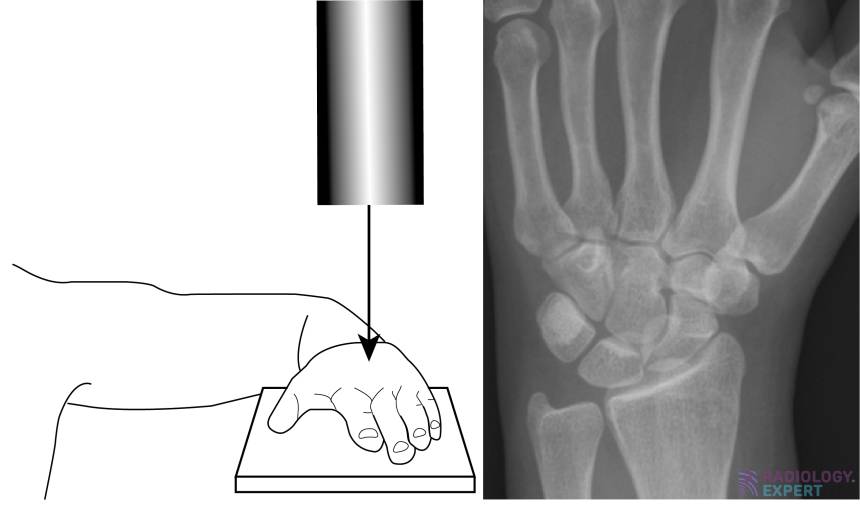

From www.radiology.expert

XWrist X Wrist Instructions High blood pressure can cause stroke, heart attack and dementia, to name a few. Please read the user manual for clear instructions on how to accurately measure your bp. X Wrist Instructions.